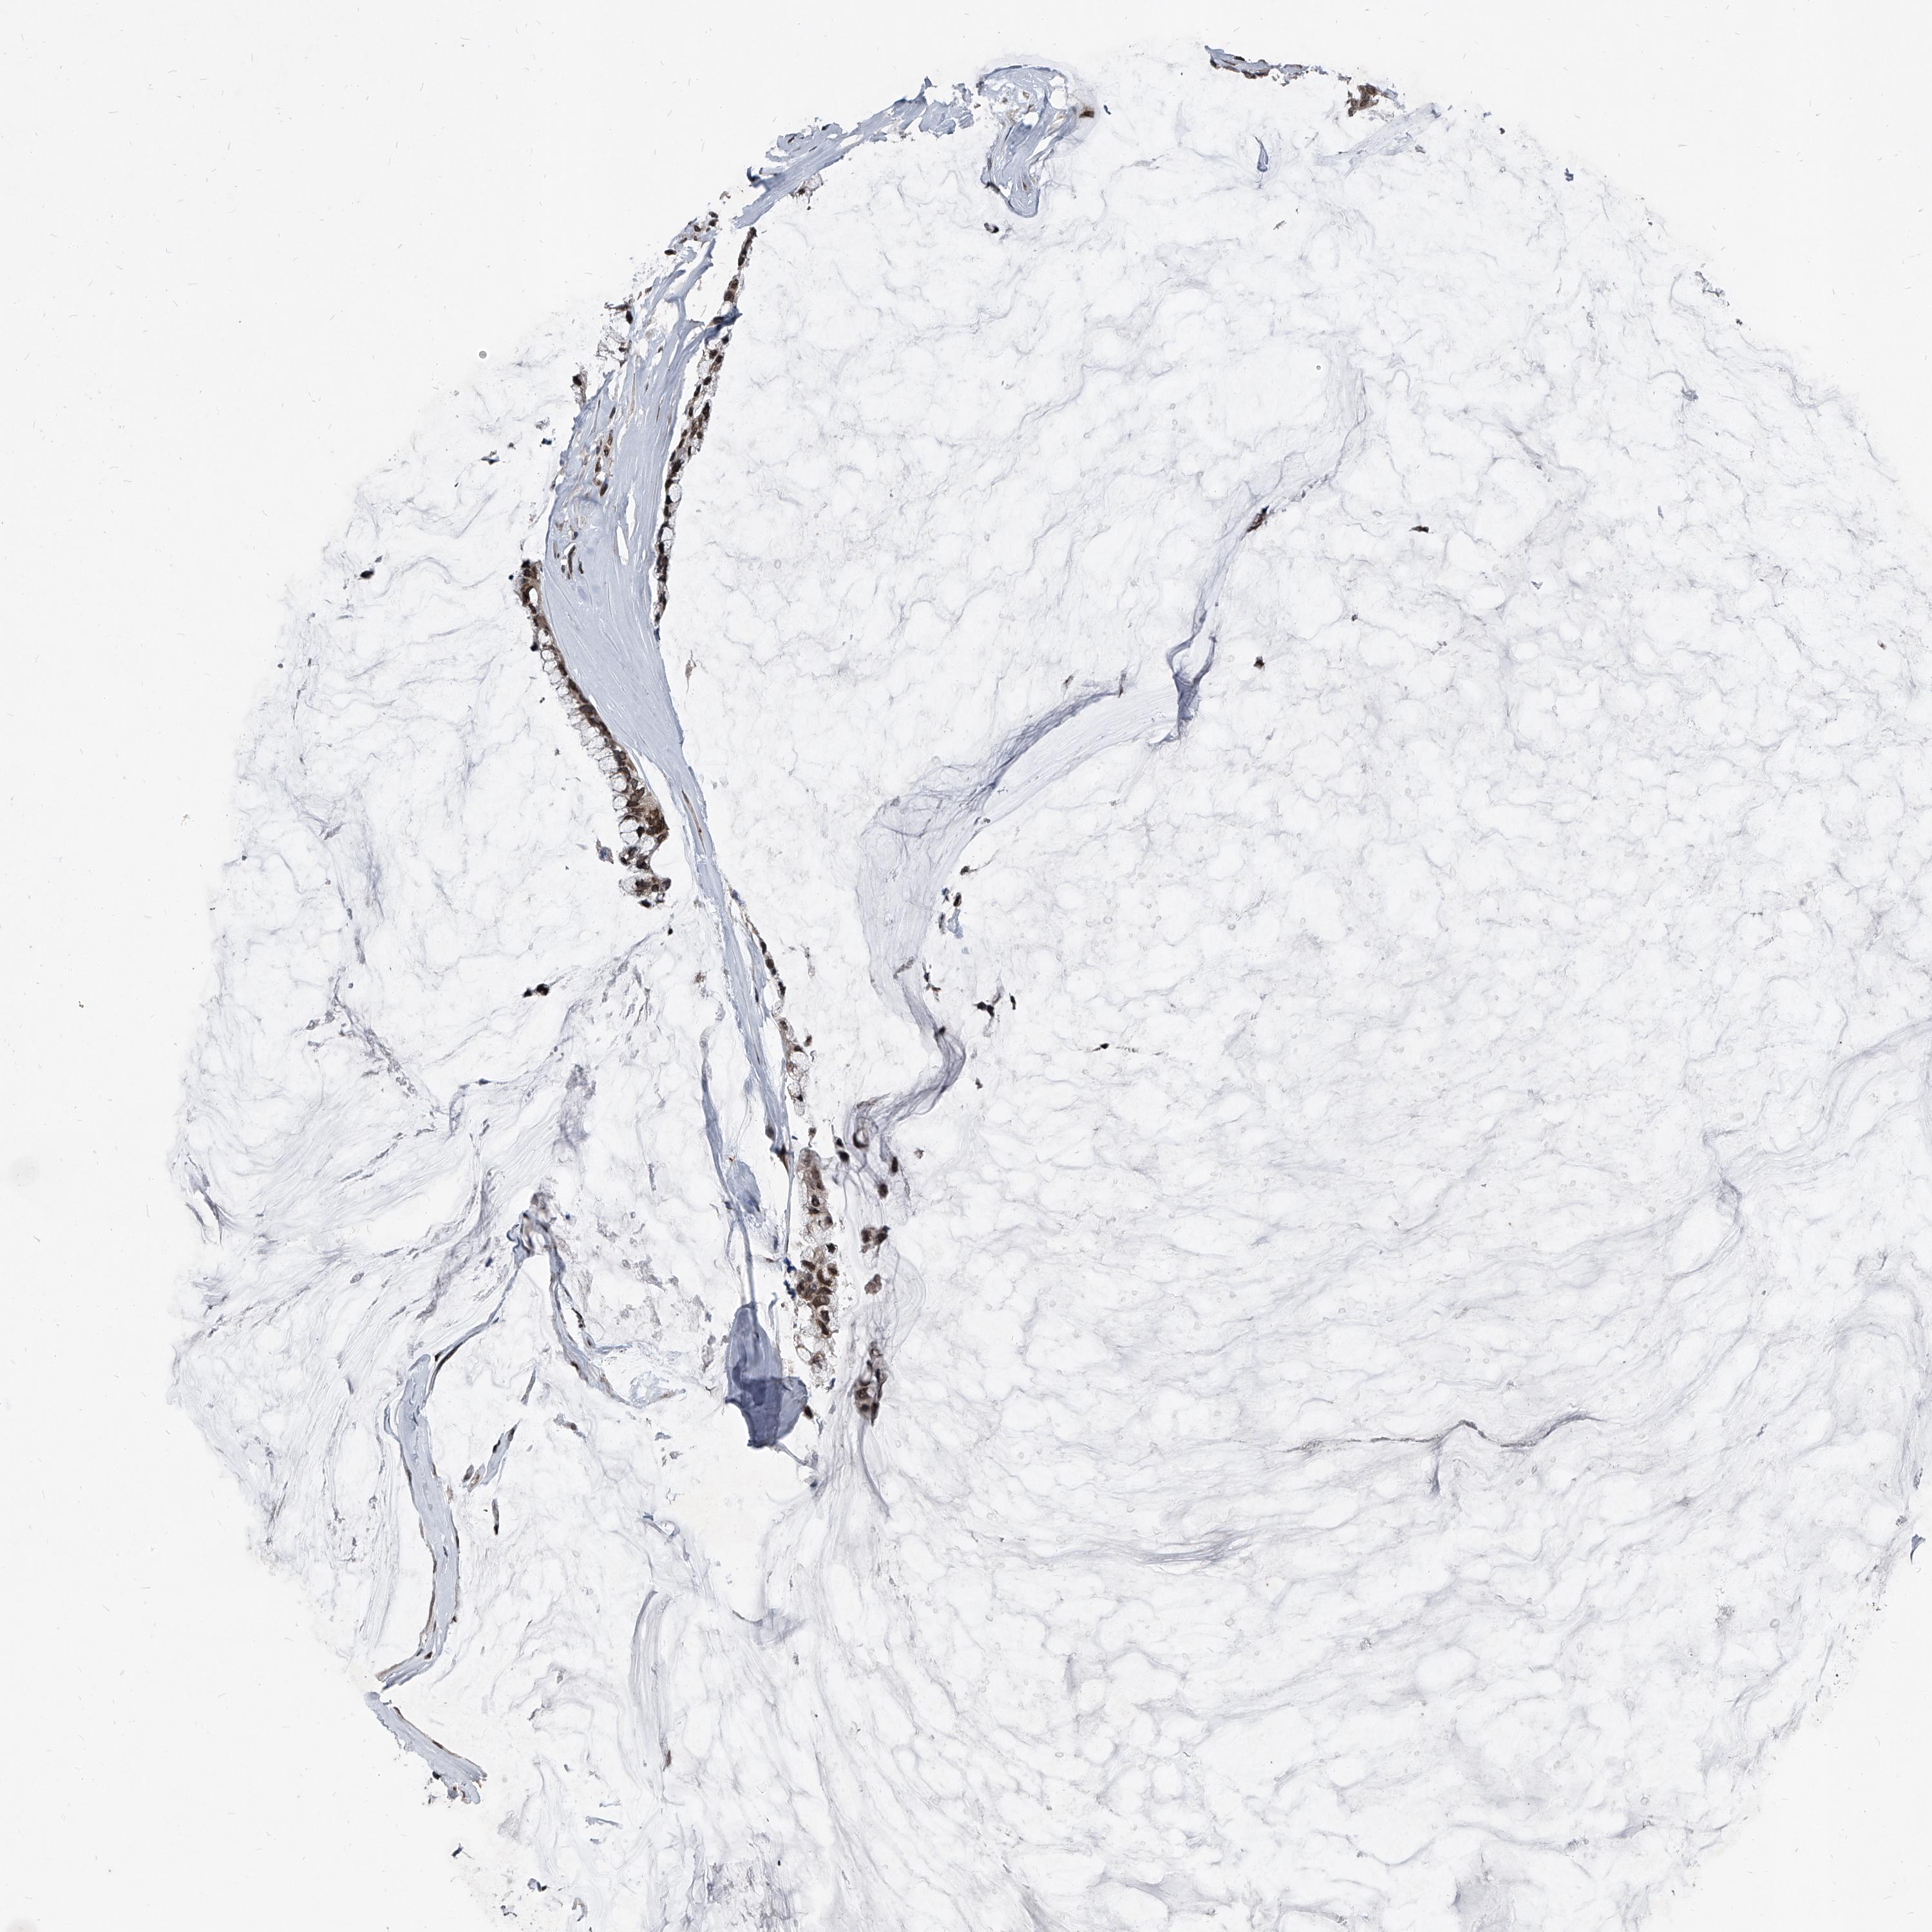

PHF20